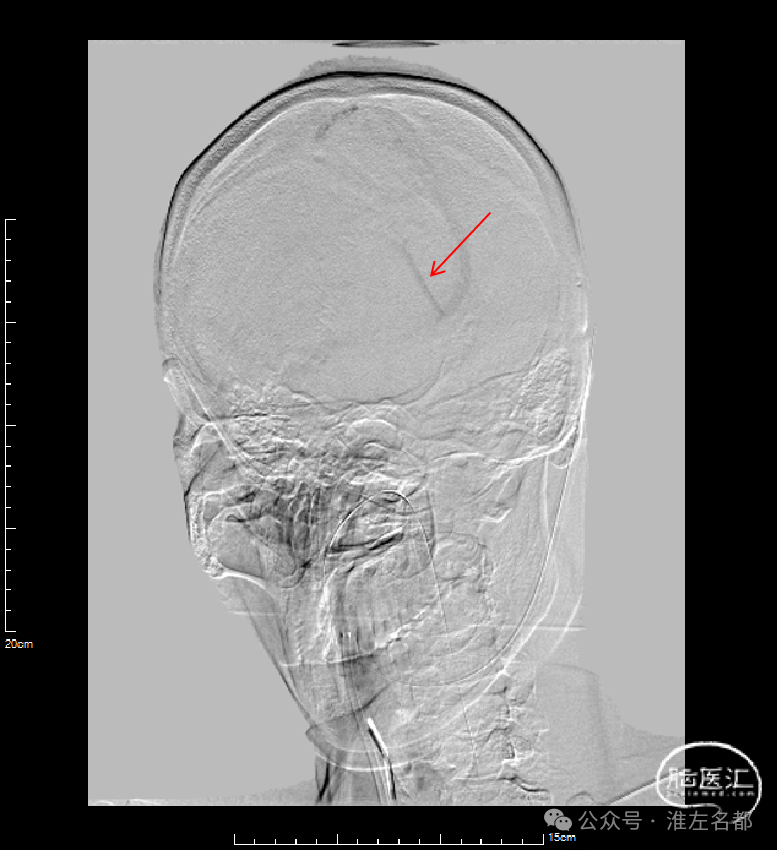

介入治疗后右侧颈动脉造影:上矢状窦、直窦和右侧横窦-乙状窦均见显影,右侧横窦局部狭窄明显。

CTV:上矢状窦、直窦、右侧横窦-乙状窦再通显影,右侧横窦局部管腔狭窄明显。